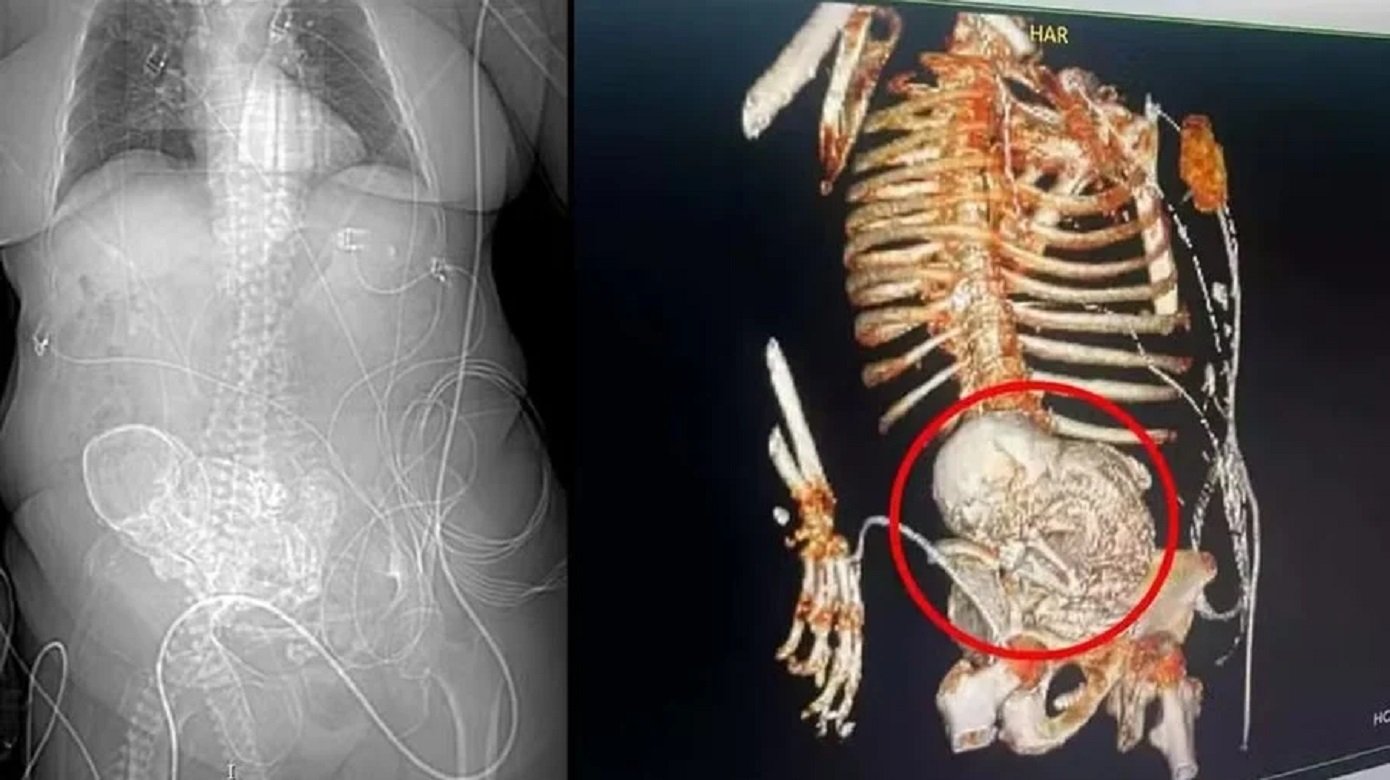

Caso raríssimo

Idosa de 81 anos carregou ‘bebê de pedra’ no ventre por mais de 50 anos, no MS

A situação aconteceu no dia 14 de março deste ano, quando uma tomografia revelou a presença do feto ...